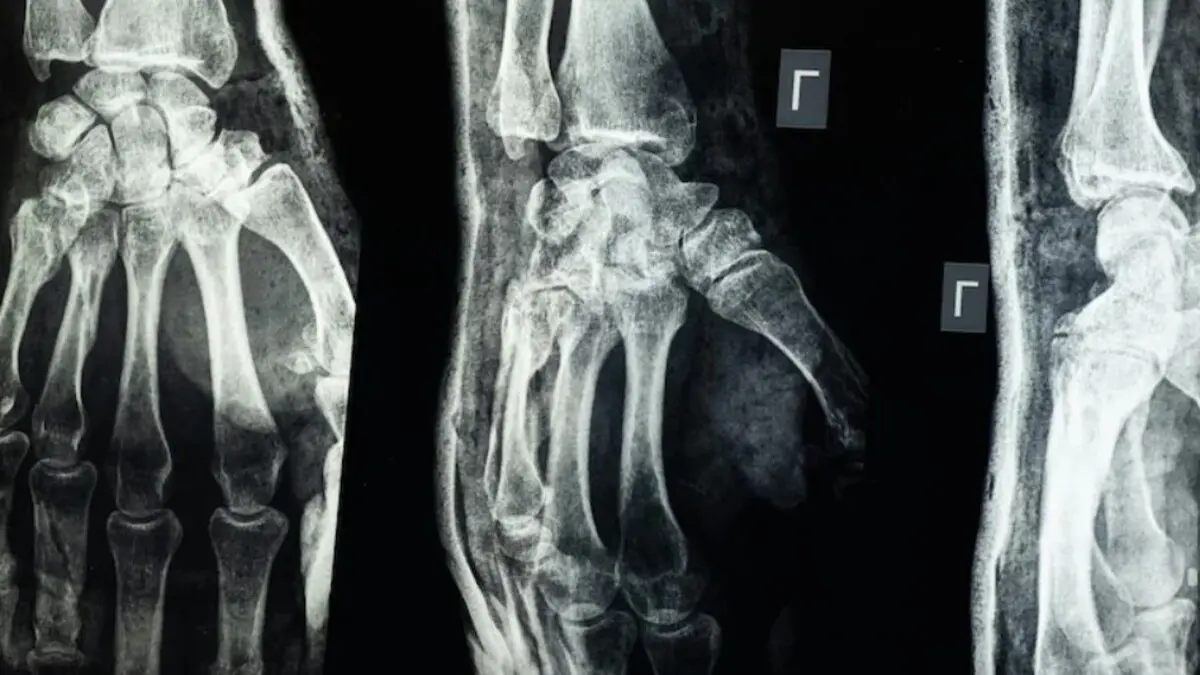

أعلن فريق بحثي في مقاطعة تشيجيانغ شرق الصين عن ابتكار طبي غير مسبوق يتمثل في غراء عظمي يحمل اسم Bone-02، قادر على معالجة الكسور وتثبيت الشظايا العظمية خلال ثلاث دقائق فقط، في خطوة وُصفت بأنها اختراق علمي في عالم جراحة العظام، وفق ما أوردته وسائل إعلام دولية بينها “إن دي تي في” و”غلوبال تايمز”.

وكشفت الاختبارات المعملية أن الغراء حقق قوة ربط تفوق 400 رطل، وقوة قص تبلغ نحو 0.5 ميغاباسكال، إضافة إلى قوة ضغط تقارب 10 ميغاباسكال. كما أظهرت التجارب السريرية على أكثر من 150 مريضًا نتائج ناجحة، ما يعزز الآمال في أن يشكّل بديلًا آمنًا وفعالًا عن الطرق التقليدية.